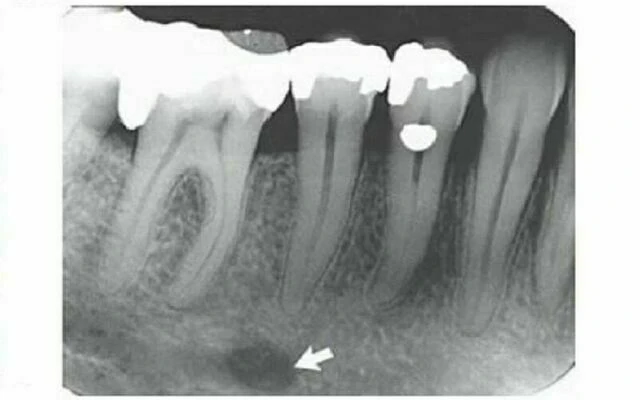

Lỗ cằm thường là giới hạn phía trước của ống thần kinh răng dưới xuất hiện trên phim quanh chóp. Hình ảnh của nó khá khác nhau, và có thể chỉ được xác định thấy trong một nửa trường hợp vì miệng của lỗ cằm hướng về phía trên và ra sau. Do đó hình ảnh nhìn thấy ở vùng răng cối nhỏ không phải là hình chụp xuyên qua trục dọc của miệng ống. Cấu trúc giải phẫu này khiến cho hình ảnh lỗ cằm khác nhau. Mặc dù thành lỗ được cấu tạo từ xương vỏ nhưng mật độ hình ảnh lỗ cằm khá khác nhau về hình dạng lẫn bờ viền. Nó có thể hình tròn, hình thuôn, hình khe hoặc không đều và cấu tạo một phần hoặc phủ toàn bộ bởi xương vỏ. Lỗ cằm được thấy ở ½ khoảng giữa từ bờ dưới xương hàm dưới đến mào xương ổ răng, thường ở vùng chóp răng cối nhỏ thứ hai. Ngoài ra, vì nằm trên bề mặt của xương hàm dưới, mối liên hệ giữa ví trí hình ảnh của nó với các chân răng phụ thuộc vào góc chụp. Nó có thể nằm bất cứ vị trí nào từ phía gần chân răng cối lớn thứ nhất hàm dưới đến xa nhất ở phía trước là mặt gần chân răng cối nhỏ thứ nhất . Đôi khi có thể quan sát thấy hình ảnh hai lỗ cằm, một lỗ nằm phía trên lỗ kia.

Khi lỗ cằm nằm trên chóp răng cối nhỏ, nó có thể bắt chước hình ảnh tổn thương của bệnh lý quanh chóp. Trong những trường hợp này, bằng chứng cho thấy ống thần kinh răng dưới kéo dài đến vùng thấu quang nghi ngờ hoặc nhìn thấy có lamina dura ở răng, những điều này gợi ý bản chất thật của vùng thấu quang là gì. Tuy nhiên, cần chỉ rõ ra rằng đường lamina dura mảnh chồng lên lỗ thấu quang có thể làm giảm đáng kể hình ảnh lamina dura, nên sẽ khó xác định sự hiện diện của nó hơn. Mặc dù vậy, một phim X quang thứ hai chụp từ một góc độ khác sẽ cho thấy rõ hình ảnh lamina dura, cũng như sự thay đổi vị trí lỗ thấu quang so với chóp răng.